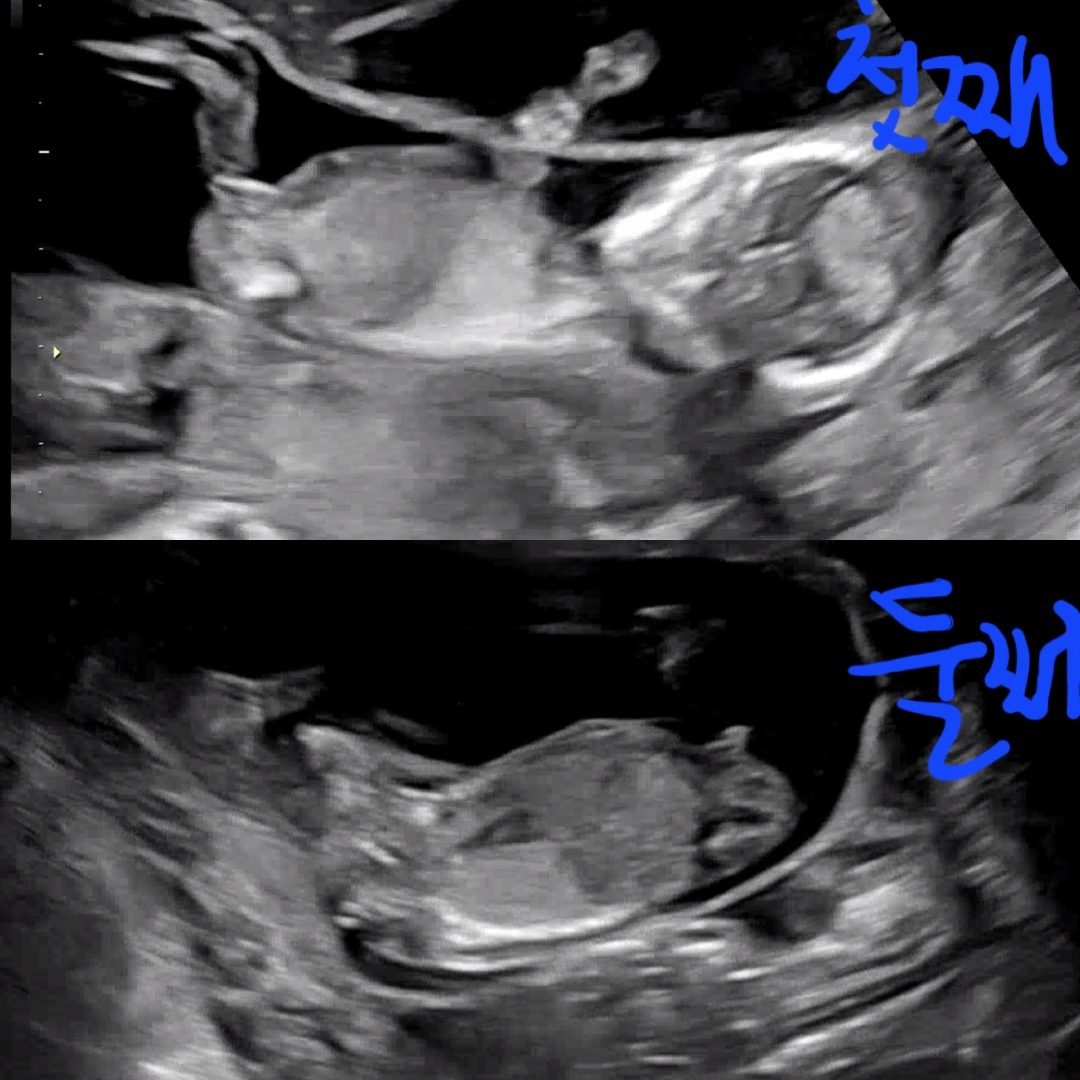

우리 둥이들 성별 한번만 봐주세요🙏

3주뒤에 병원가는데 그동안 너무 궁금하네요🥲 성별 글 지겨우시겠지만 한번만 확인 부탁드려요

각도로는 딸,아들 같아욥!

둘째는 잘안보이는거 같구 첫째는 딸한표용